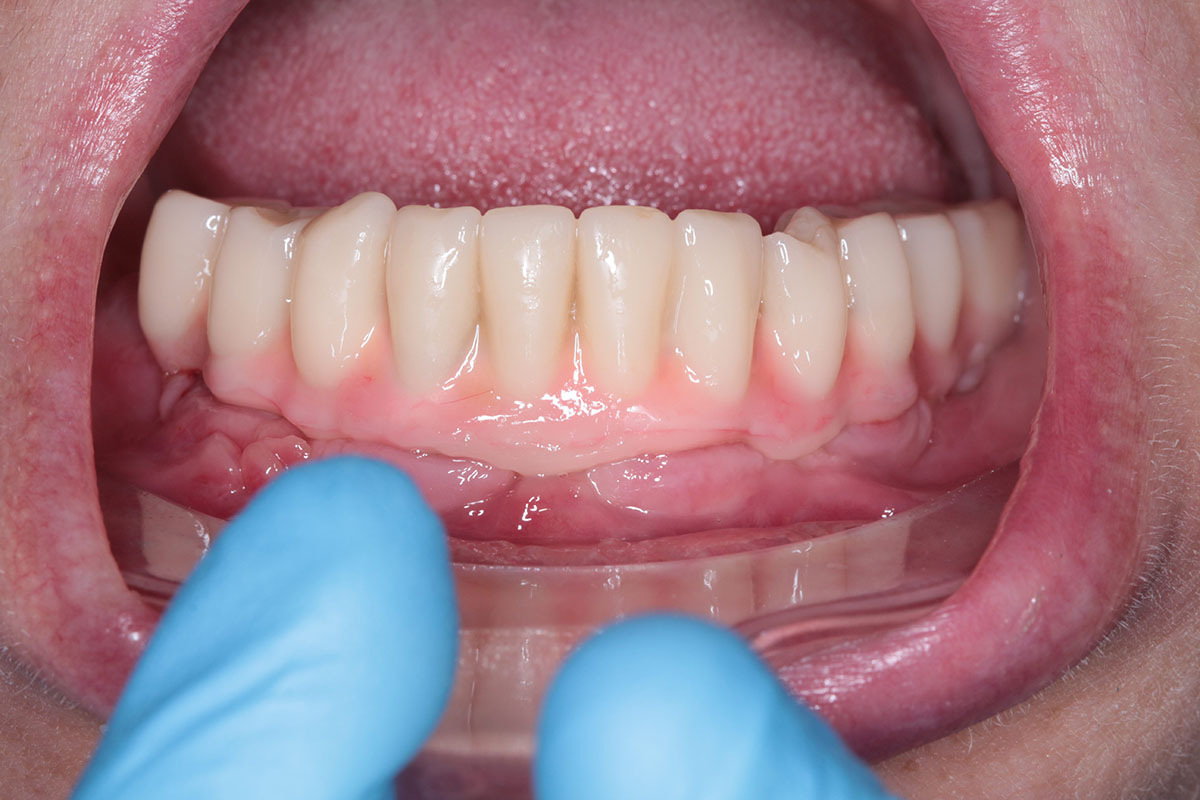

Ортопедичний етап

Лікар встановлює мульти-юніт абатмент на титанові імплантати. І лише тоді знімає зліпок та створює майбутню ортопедичну конструкцію.

Новий протез ставлять відразу або в день операції, або протягом 3-7 діб. Лікар складає рекомендації щодо догляду за тимчасовим протезом, розповідає про обмеження на період адаптації та визначає дату контрольного прийому. Протягом шести місяців імпланти повністю приживаються. Після цього можна встановити постійний протез.

Максимально природний вигляд коронок за естетичними чинниками забезпечують безметалеві варіанти з діоксиду цирконію. Вони не фарбуються при їжі та гіпоалергенні. Для жувальних зубів краще підходить металокераміка, яка витримує навантаження при пережовуванні твердих продуктів.